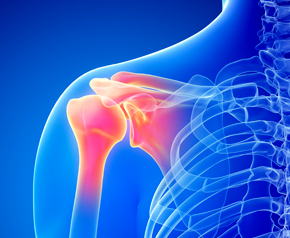

오십견과 회전근개파열의 증상 비교

회전근개파열

· 누군가가 팔을 올려주면 잘 올라간다.

· 팔을 움직일 때 특정 각도나 방향에서만 통증이 발생한다.

· 주로 어깨 위쪽, 앞쪽에서 통증이 발생한다.

· 팔의 근력이 약화된다.

오십견

· 누군가가 도와줘도 팔을 올릴 수 없다.

· 팔을 움직일 때 모든 각도와 방향에서 통증이 발생한다.

· 어깨 뒷쪽에서 전체적으로 통증이 발생한다.

· 팔의 근력과는 연관이 없다.